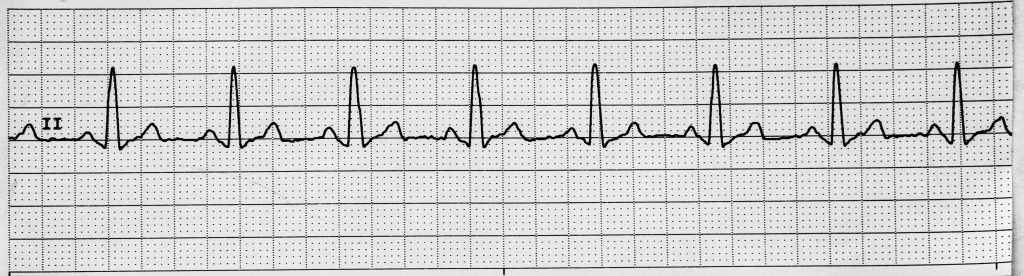

Rhythm #3 of 20